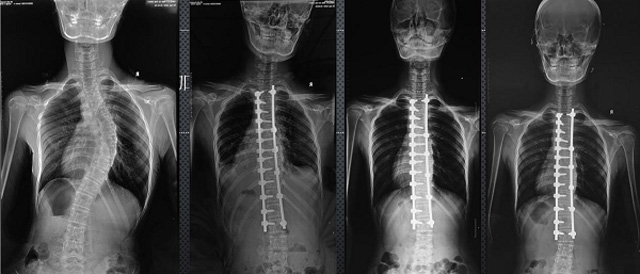

(7)全身拚接功能對有較大尺寸全脊柱拚接圖接桂成金下股分成幾次拍攝,再經過秋件開在骨科開展的全脊柱畸形矯治工作中,雖然CT. MRI也能獲取全脊柱影像,接圖像,以便於長度、角度、力線等測量和察脊柱在重力情況下但不能進行立位檢查,無法觀全景觀察。全身拚接功能是高等級DR攝取患者立位全下的功能狀態圖像,因此采用動態醫院特別看重的動態DR功能之一。注:圖中Cobb脊柱正側位圖像是首選的檢查方法角度的大小是反映側彎嚴重程度的一個標準。